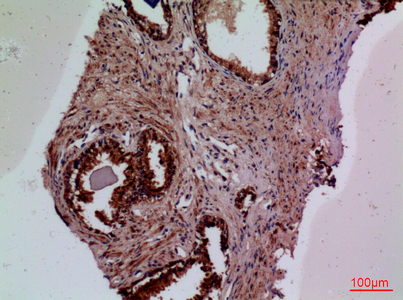

WB,IHC-P,IF-P,IF-F,ICC/IF,ELISA

WB 1:500-1:2000, IHC-P 1:100-300, ELISA 1:20000, IF-P/IF-F/ICC/IF 1:50-200